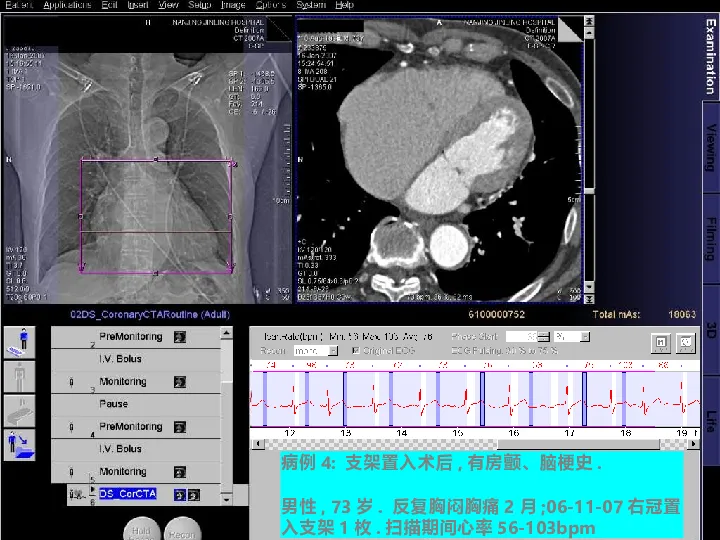

>【影像PPT】双源CT及其临床应用

【影像PPT】双源CT及其临床应用